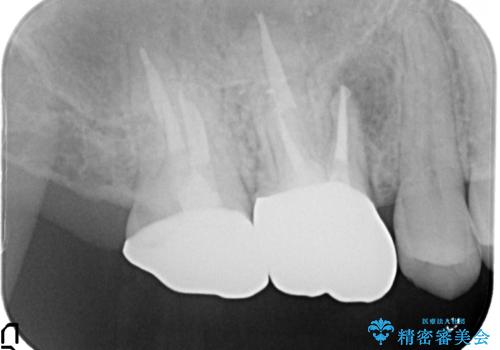

根っこの感染 再治療をしてかぶせ物を製作する

- 古いかぶせ物・土台・根管充填材をすべて除去し、内部を徹底的に洗浄する

→改めて土台を築造し、かぶせ物を新製する

根管治療を丁寧に仕上げることで、長く安心してかぶせ物を使っていただくことができます。